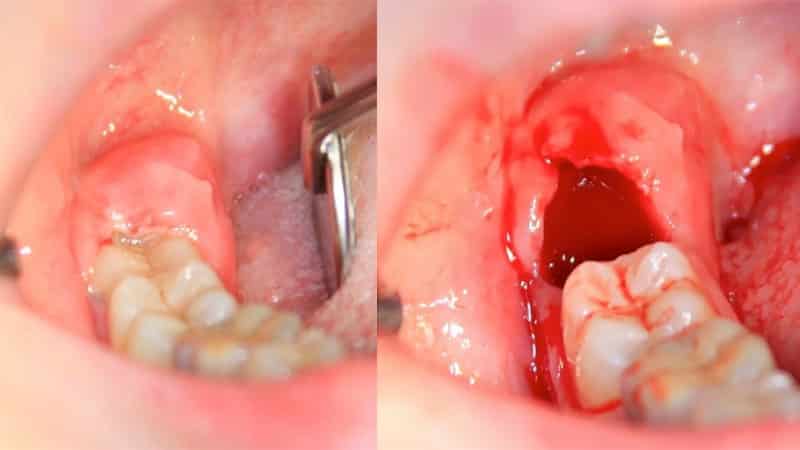

Раннее удаление «капюшона», который мешает нормальному росту мудрого зуба, может предотвратить такие опасные осложнения. Признаки роста зуба мудрости можно определить по его боли. Если появляются сильные отеки в области мудрого зуба, сопровождающиеся повышенной температурой тела, следует незамедлительно обратиться к специалисту. Эти симптомы могут указывать на развитие перикоронарита (воспаления «капюшона» десны). Если не начать лечение вовремя, процесс может осложниться абсцессом, который, в свою очередь, без должного лечения вызывает сепсис — опасное заболевание, угрожающее жизни. При своевременном обращении к стоматологу, специалист направит пациента на рентгенологическое обследование, которое поможет выявить и лечить патологию, предоставив полную картину расположения зубов.

Существует распространенное заблуждение, что «восьмерки» всегда вызывают проблемы, но это не соответствует действительности. У некоторых людей они прорезываются безболезненно в течение нескольких дней или недель, но большинство испытывает дискомфорт. Это связано с тем, что зубы мудрости появляются, когда челюсть полностью сформирована, но с возрастом она немного сужается и размеры ее уменьшаются. В результате прорезывания зубов мудрости может возникать перикоронарит, вызывающий хроническое разрастание фиброзной ткани, болезненность и отек слизистой оболочки над зубом. Это состояние требует хирургического лечения.

Также не рекомендуется применять тепло к десне или полоскать рот горячими растворами, чтобы не распространять патологический процесс на соседние ткани. После удаления «капюшона» зуба мудрости, рекомендуется полоскать рот антисептическим раствором, чтобы предотвратить инфекцию открытой раны.